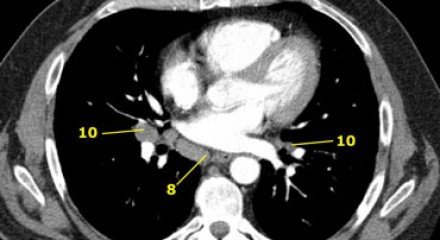

8. Linfonodos Paraesofageanos

Estes linfonodos estão abaixo dos linfonodos carinais e se estendem caudalmente até o diafragma.

9. Linfonodos do ligamento Pulmonar

Linfonodos do ligamento pulmonar estão dentro do ligamento pulmonar, incluindo aqueles na parede posterior e inferior da veia pulmonar inferior.

O ligamento pulmonar é a extensão inferior das reflexões da pleura mediastinal que cercam o hilos.